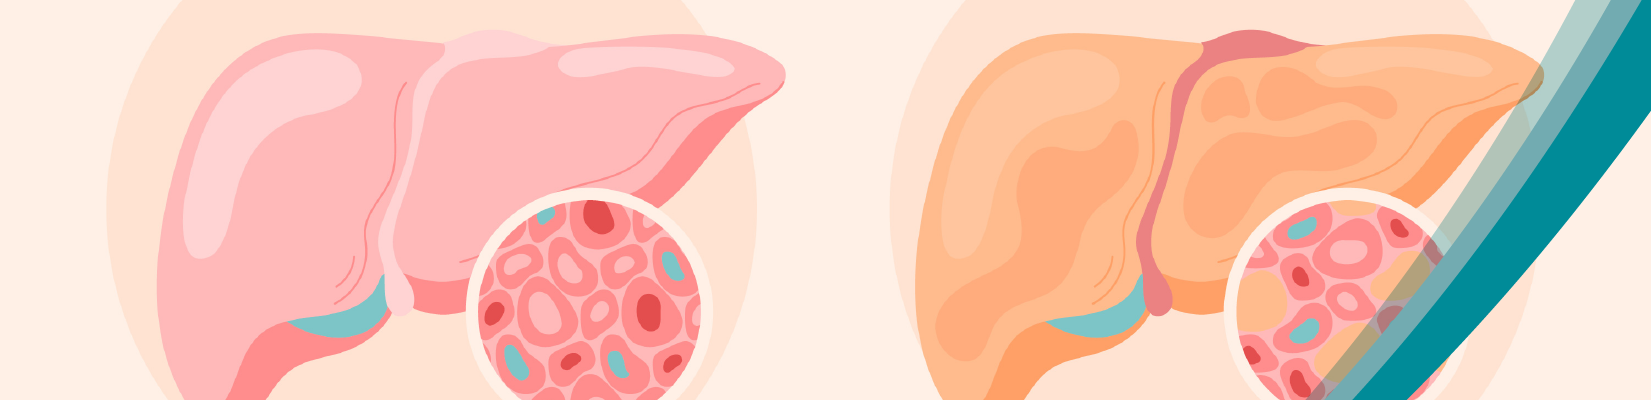

Liver disease constitutes a group of conditions that can be caused due to infections, inherited, obesity or alcohol abuse. Liver cirrhosis is a commonly used term that refers to the scarring of the liver over a course of time. As more scarred tissue replaces healthy tissue, it impacts the normal functioning of the liver leading to liver failure and liver cancer.

Non-alcoholic Fatty Liver disease (NAFLD) is a term for a range of conditions caused by the build-up of extra fat in the liver cells. NAFLD is also associated with an increased risk of serious health problems such as diabetes, high BP and kidney disease.